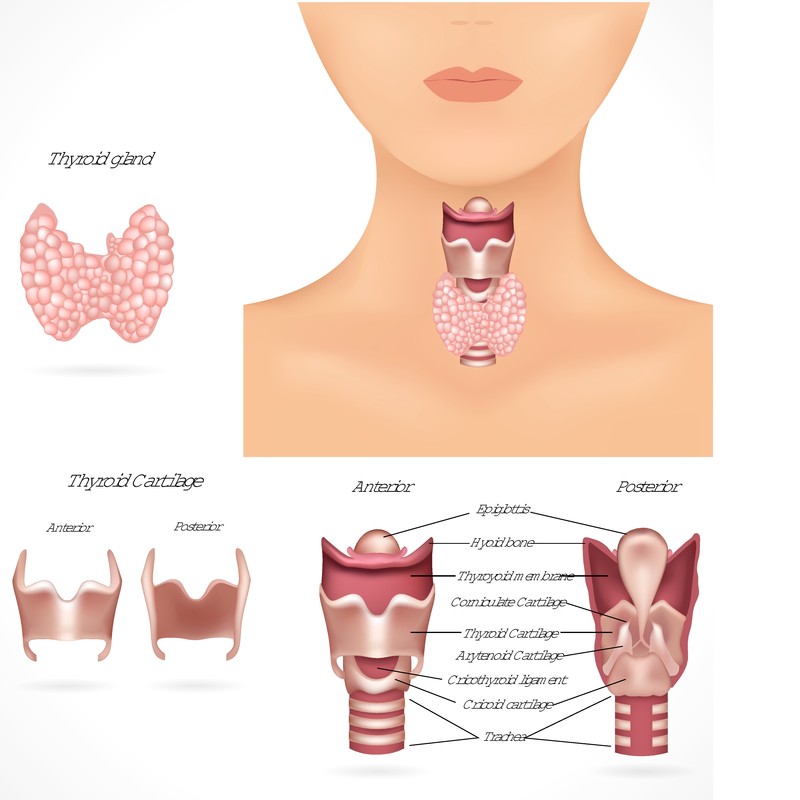

Uno de los principales riesgos de no realizarse el tamiz neonatal es la posibilidad de que el bebé desarrolle una enfermedad grave que no sea detectada a tiempo. Muchas de las enfermedades que el tamizaje neonatal identifica no presentan síntomas evidentes en los primeros días de vida, pero si no se tratan a tiempo, pueden tener efectos irreversibles. Trastornos como el hipotiroidismo congénito, la fenilcetonuria, y la fibrosis quística, entre otros, pueden ser gestionados y tratados adecuadamente si se detectan temprano. Sin embargo, sin esta prueba, el diagnóstico puede retrasarse, lo que aumenta el riesgo de complicaciones a largo plazo.

Al no realizar el tamiz neonatal, el bebé también corre el riesgo de enfrentar complicaciones a largo plazo que podrían haberse evitado con un diagnóstico temprano. Trastornos como el hipotiroidismo congénito pueden afectar el crecimiento y el desarrollo de los niños si no se tratan de inmediato. El tratamiento temprano con hormonas tiroideas puede permitir que el niño se desarrolle normalmente, pero si se retrasa, puede haber problemas permanentes con el crecimiento y el desarrollo cognitivo.